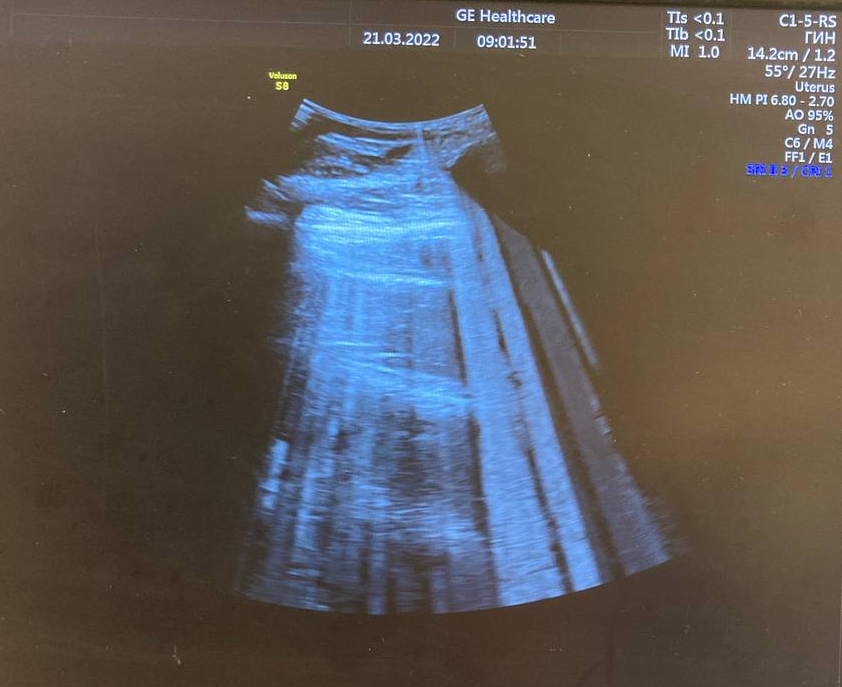

GE Voluson S8 BT18 Ремонт платы DBM128G ASSY (PN:5573638-2) Дата: 26.03.2022 🔧 Заявленная неисправность: В нашу лабораторию компонентного ремонта поступила плата DMB128G ASSY (PN: 5573638-2) от аппарата Voluson S8 BT18. На обложке этого выпуска как раз показаны помехи и артефакты, которые проявляются во время работы с любым датчиком.

В нашу лабораторию компонентного ремонта поступила плата DMB128G ASSY (PN: 5573638-2) от аппарата Voluson S8 BT18. На обложке этого выпуска как раз показаны помехи и артефакты, которые проявляются во время работы с любым датчиком.

Проблема, которую наблюдал клиент на аппарате Voluson S8 - довольно частая. Подобные помехи и артефакты проявляются на аппаратах Voluson S6 (BT11, BT12, BT14, BT16, BT18), Voluson S8 (BT11, BT12, BT14, BT16, BT18), Voluson S10 (BT16, BT18, BT22).

Ниже представлен список ультразвуковых плат, которые при поломке ведут себя как фото.